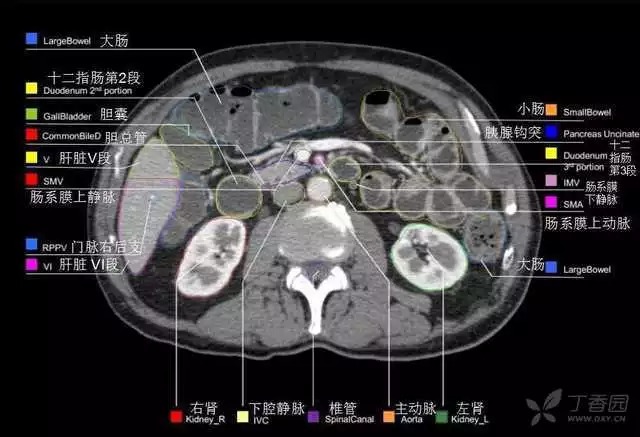

腹部肝脏高清CT断层的图谱

全腹部高清CT图谱,淋巴结彩色图谱,血管解剖图谱大汇总!

超声肝脏分叶及分段

肝脏分段和基本解剖学标志